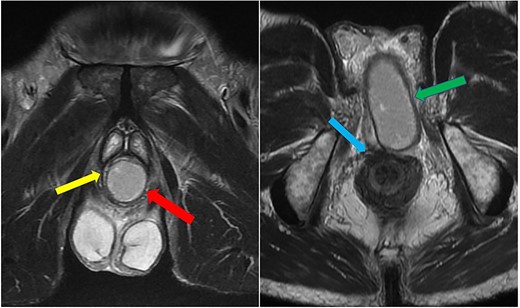

Case 2: coronal and axial T2-weighted images demonstrating the collection (red and green arrows) significantly compressing the urethra and corpus spongiosum (yellow arrow) to the right of the midline, and close to, but not involving, the anal sphincter (blue arrow).